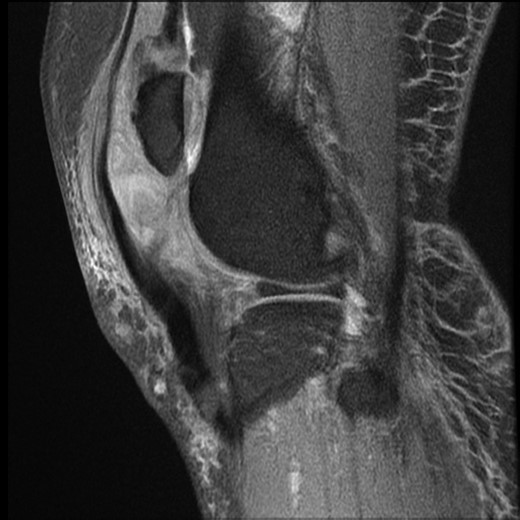

Physical examination showed knee swelling, a high riding patella with a palpable gap below the patella. The patient was unable to weight bear and could not perform active knee extension on his right knee. There was no obvious laceration or injury to the knee. Neurovascular examination was normal. Apart from ectopic ossification of the patellar tendon, plain radiograph showed no evidence of acute fracture or joint effusion (Fig. 1). Because of the unusual mechanism of injury and the initial ultrasound performed in A&E which suggested a rupture of the quadriceps and patella tendon, magnetic resonance imaging (MRI) was performed and demonstrated complete rupture of the patellar tendon from the inferior pole of patella, an almost complete shearing of quadriceps tendon off the patella and chronic tendinosis in the mid-portion of patellar tendon (Fig. 2).

MRI right knee. Sagittal T1 image. Demonstrating rupture patellar tendon attachment from inferior pole of patella, high riding patella, chronic tendinosis of patellar tendon and clustering of sheared quadriceps tendon.

Although lymphoedema following breast surgery has been associated with rotator cuff tendonitis/tear [7]; so far, the association between lymphoedema and rupture of the knee extensor apparatus has not been documented in the literature. Herrera and Stubblefield [7] first described the pathophysiology of rotator cuff tendonitis secondary to lymphoedema following axillary clearance breast cancer surgery. They believed the increased size and weight on the upper limb caused by interstitial stagnation of protein-rich fluid lymphoedema subjects the rotator cuff tendons to impingement, functional overload and intrinsic tendinopathy. With vascular studies demonstrating the presence of a hypovascular zone in quadriceps tendon (1–2 cm from superior pole of patella) frequently associated with spontaneous rupture [8], and the MRI image in our patient showing chronic tendinosis of the patellar tendon (Fig. 2), it is most likely that chronic lymphoedema was the main aetiological factor in this spontaneous non-traumatic bifocal injury of the knee extensor apparatus. This is likely secondary to the resultant chronic inflammation and fibrosis from chronic lymphoedema, which compromised perfusion and tendon/connective tissue homeostasis, therefore predisposing the retinaculum, quadriceps and patellar tendon to a risk of rupture.